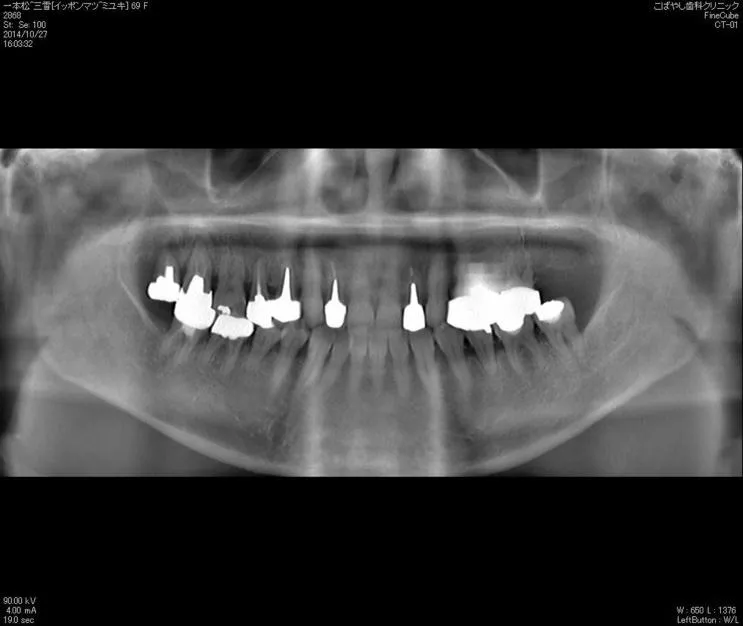

レントゲン検査

歯周病の進行にともない、歯槽骨が溶けていきます。レントゲンによって歯槽骨の状態を検査し、症状の進行段階を確認します。

治療中